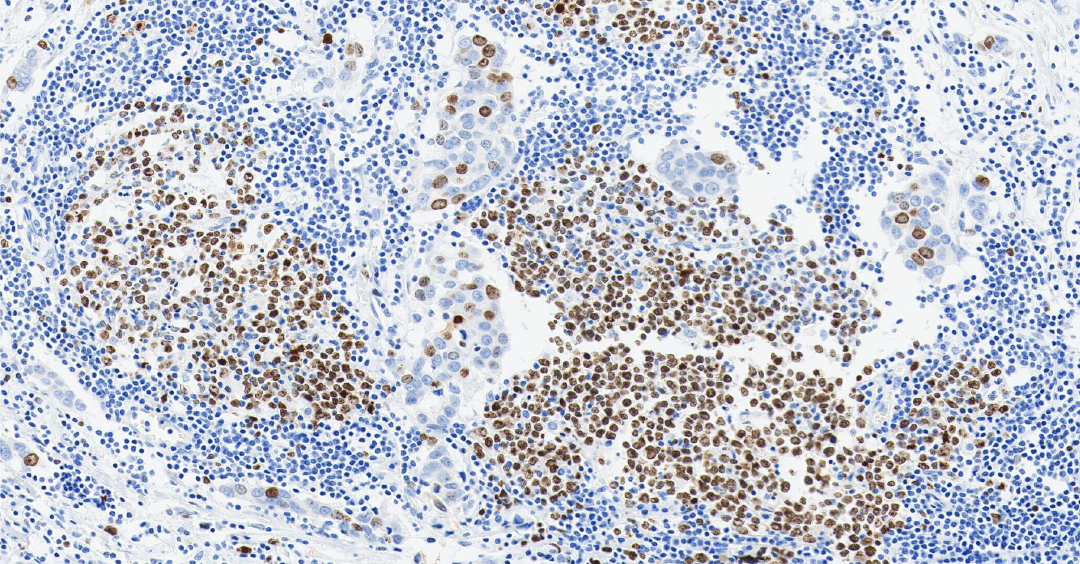

TTF-1

TTF-1 ——甲状腺转录因子-1,属于 NKX2 转录因子家族。

定位: 细胞核。

功能: TTF-1 是调控肺组织和甲状腺器官特异性基因表达的核转录因子,对肺泡上皮细胞的终末分化和表面活性物质的分泌至关重要。

TTF-1 是关键的核转录因子,表达具有高度组织特异性。它在肺腺癌和甲状腺癌中高表达,是诊断这些原发癌的核心标志物 [3] 。 其临床价值在于鉴别转移癌的原发部位:若 TTF-1 阳性,强烈提示肿瘤来源于肺或甲状腺。值得注意的是,肺鳞癌中 TTF-1 通常为阴性,需结合其他标志物来进一步确认[4]。

图 2.人肺癌组织的 TTF-1 免疫组化分析[5]。